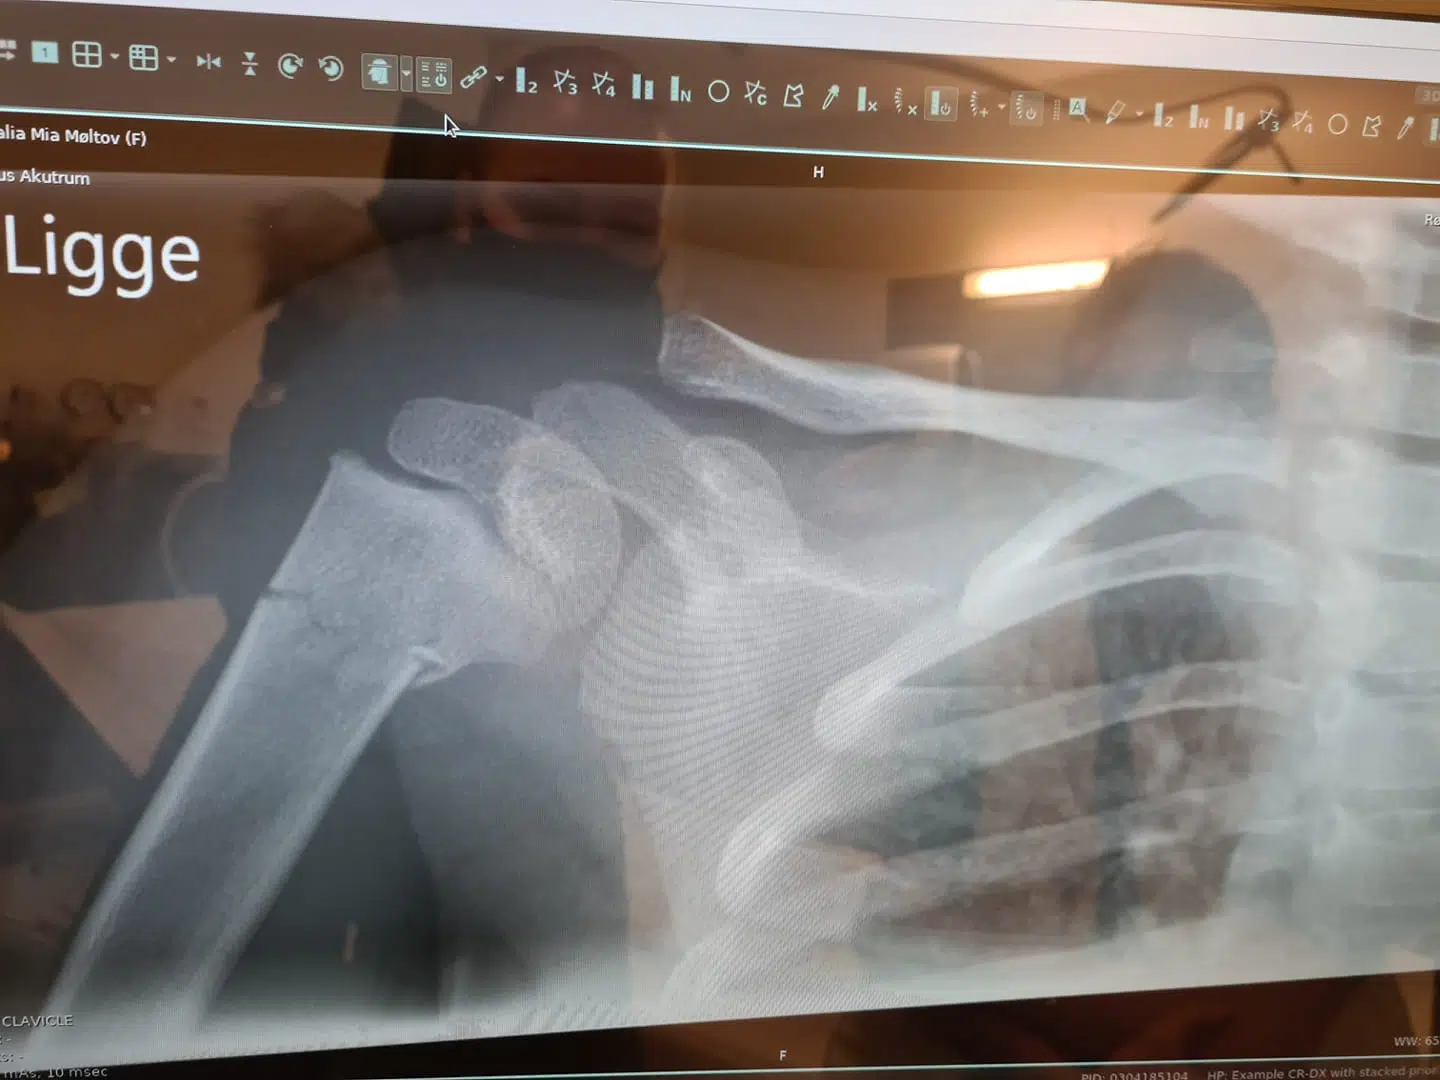

Efter mange omveje og en hård kamp fik Amalia lavet et røntgenfoto. Og resultatet talte sit tydelige sprog:

Amalia havde et brud på højre overarm. Det havde hun gået rundt med i fem dage.